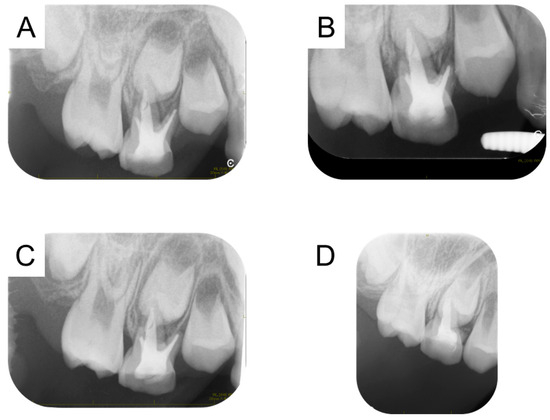

| Pk M, 2016 [27] | #84 | Mesio-lingual canal | H file | 15 months | Not listed |

| Kaul R, 2022 [28] | #85 | Disto-buccal canal | K file | 6 months | Not listed |

| Present case | #55 | Mesio-buccal canal | Reamer | 17 months | Enamel hypoplasia |